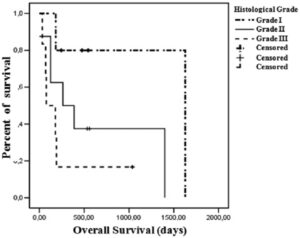

組織病理学検査は、乳腺腫瘍の診断、分類、および等級付けのゴールドスタンダードですが、麻酔をかけて腫瘍の一部を切除する必要があります。腫瘍は、腺分化、核の多形性、有糸分裂指数などの特徴に基づいて、高分化型(グレード I)、中分化型(グレード II)、または低分化型(グレード III)にグレード分けされます。

- Seixas, F., Palmeira, C., Anjos Pires, M., et al. (2011). グレードは猫乳癌の独立した予後因子である:臨床病理学的および生存率解析. Vet J. 187(1):65-71.

- Dagher, E., Abadie, J., Loussouarn, D., et al. (2019). ネコの浸潤性乳腺癌:組織学的グレーディングの予後価値. Vet Pathol. 56(5):660-70.